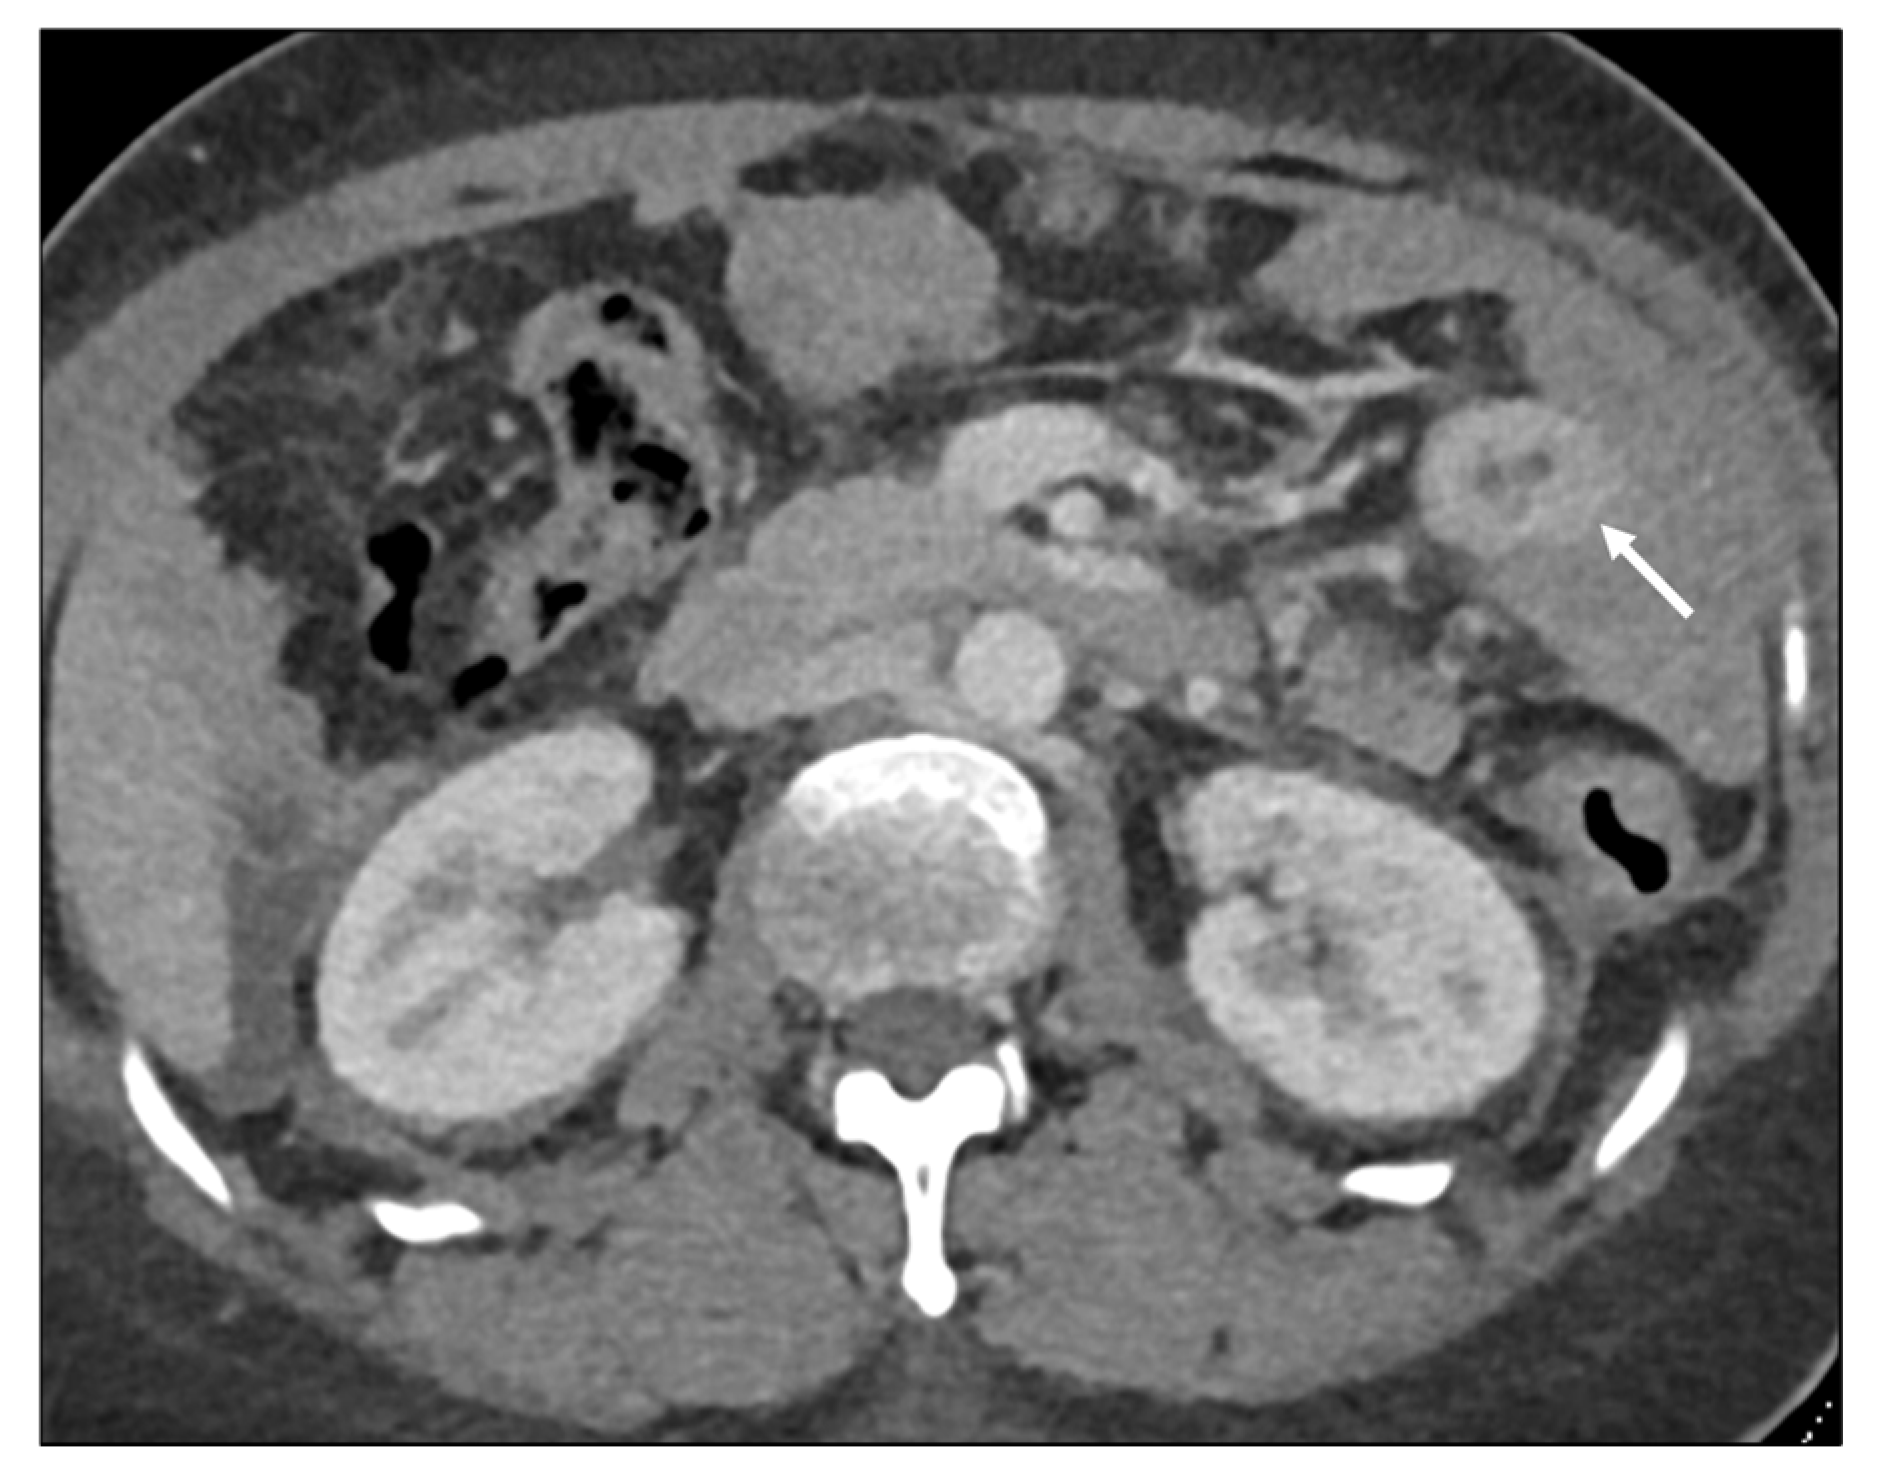

Length

- Jang, H.J.; Lim, H.K.; Kim, H.S.; Cho, E.Y.; Lee, S.J.; Kim, K.A.; Choi, D. Intestinal metastases from gastric adenocarcinoma: Helical CT findings. J. Comput. Assist. Tomogr. 2001, 25, 61–67. [Google Scholar] [CrossRef]

- Burgain, C.; Germain, A.; Bastien, C.; Orry, X.; Choné, L.; Claudon, M.; Laurent, V. Computed tomography features of gastrointestinal linitis plastica: Spectrum of findings in early and delayed phase imaging. Abdom. Radiol. 2016, 41, 1370–1377. [Google Scholar] [CrossRef]

- DiPiro, P.J.; Tirumani, S.H.; Cruz, G.P.; Ramaiya, N.H.; Lester, S.C.; Shinagare, A.B. Lobular breast cancer: Patterns of intraabdominal metastatic spread on imaging and prognostic significance. Abdom. Radiol. 2019, 44, 362–369. [Google Scholar] [CrossRef]